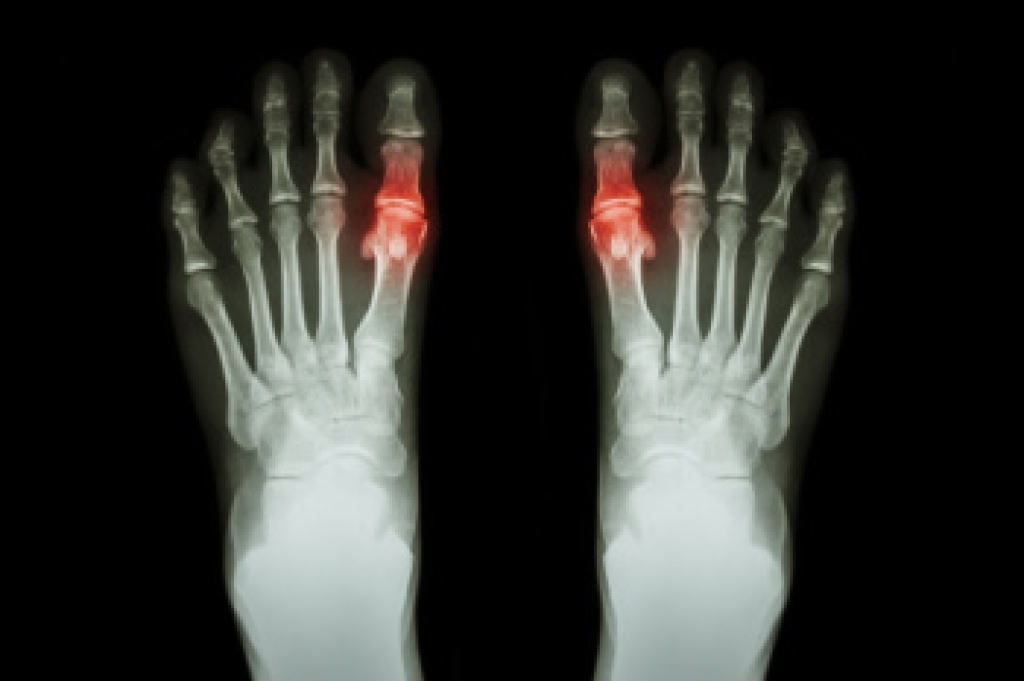

Juvenile arthritis,